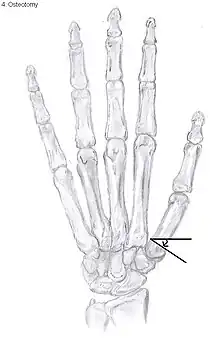

Metacarpal osteotomy

The aim of metacarpal osteotomy is to change the pressure distribution on the TMC joint. The hope is that this will slow the pace of development of osteoarthritis. There is no evidence that this procedure can modify the natural course of TMC OA. Osteotomy may be considered for people with mild arthritis.[20]

During osteotomy, the metacarpal is cut and a wedge shape bone fragment is removed to move the bone away from the hand.[31] Postoperative, the thumb of the patient is immobilized using a thumb-cast.

Possible complications are non-union of the bone, persistent pain related to unrecognized CMC or pantrapezial disease and radial sensory nerve injury.[20]